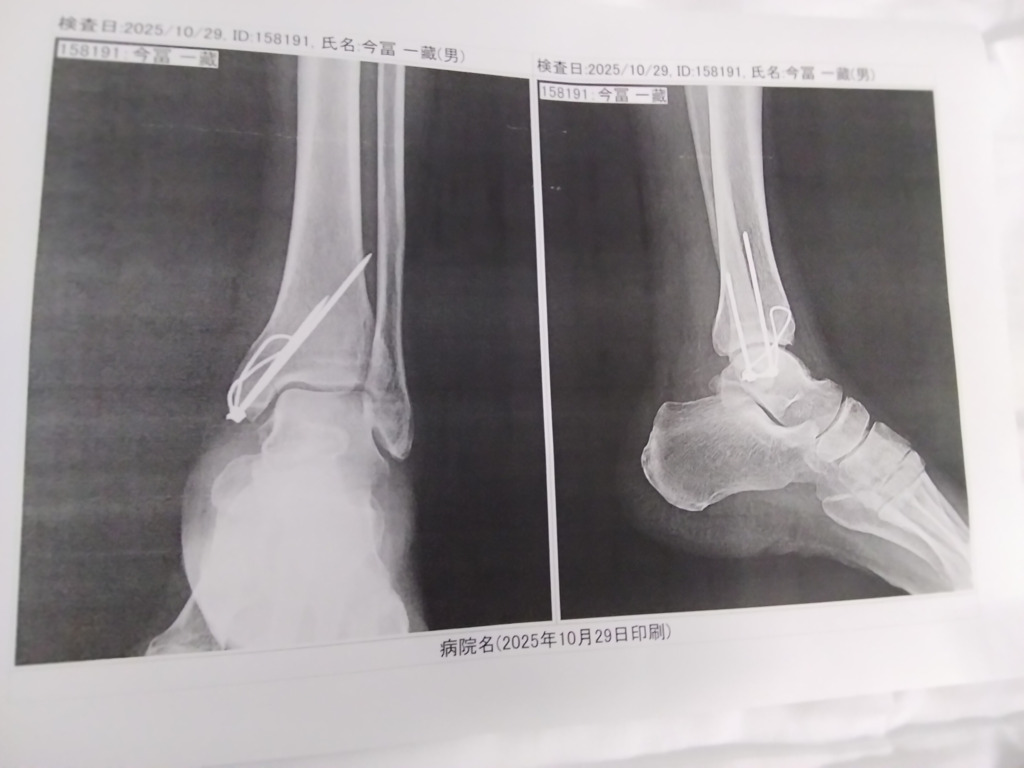

術後一週間のレントゲンを撮りました。ズレはなかった。

松葉杖も片方だけで移動出来る。😆

歩行器を使えばドリフト走行も出来るようになりました。😆